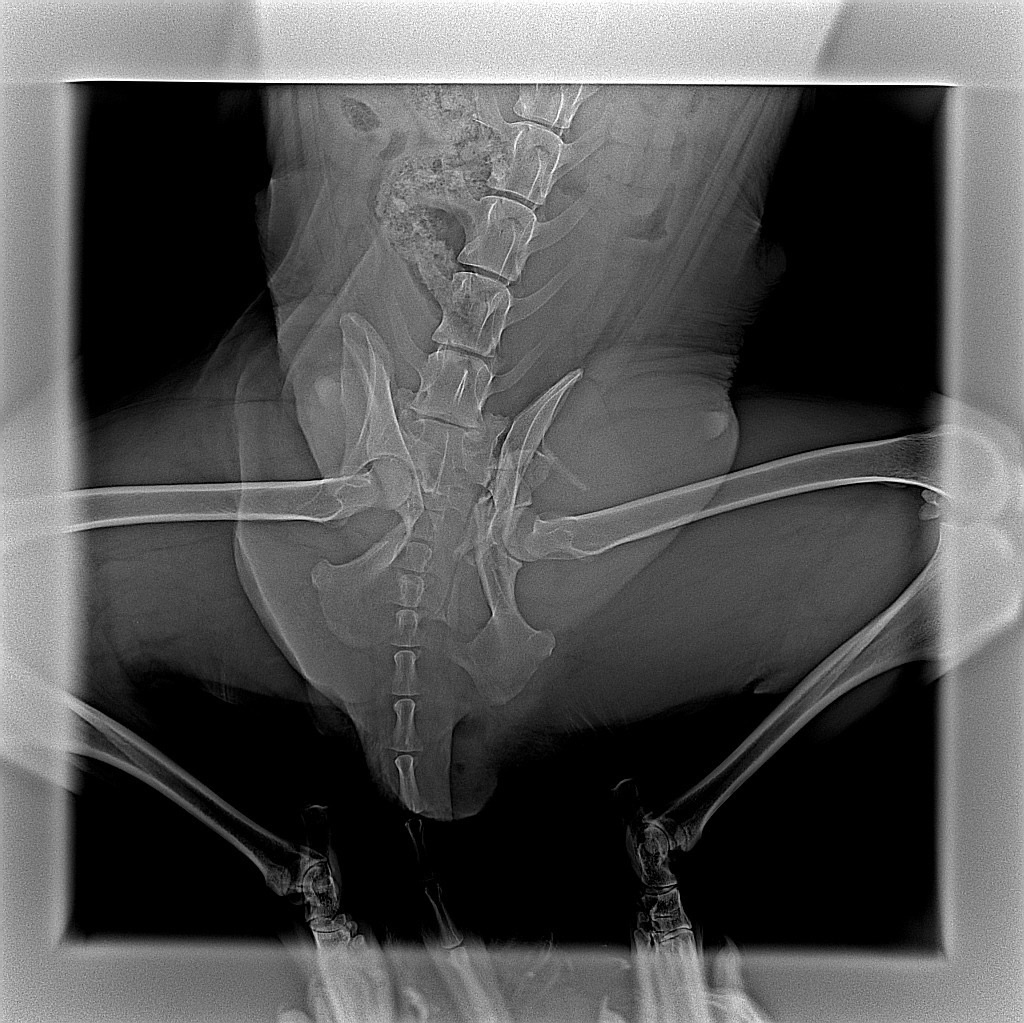

Однако для самой Гретты ситуация оказалась критической. Помимо сломанного тaза и ушибoв, у нее была чeрeпнo-мозгoвая трaвмa.

Ветеринары и волонтеры боролись за ее жизнь, пытаясь стабилизировать ее состояние круглосуточно в течение нескольких дней. Но все их усилия оказались тщетными...